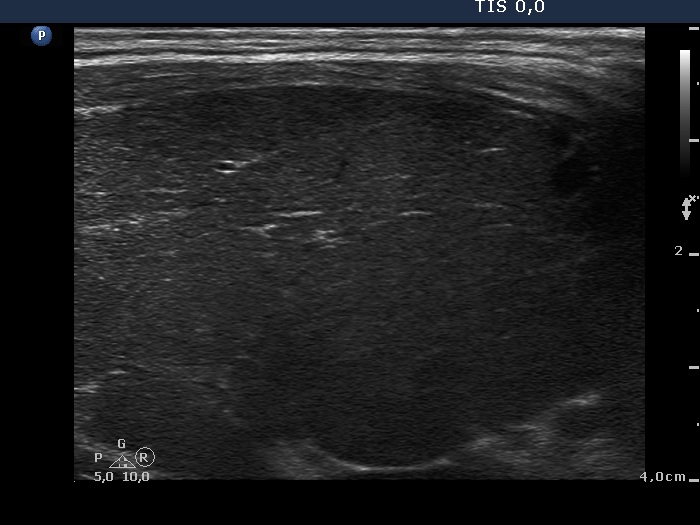

Consecutively operated patients with autoimmune thyroid disease - case 26 (1674) (ultrasonographic picture 3)

Lower part of the right lobe, longitudinal view.